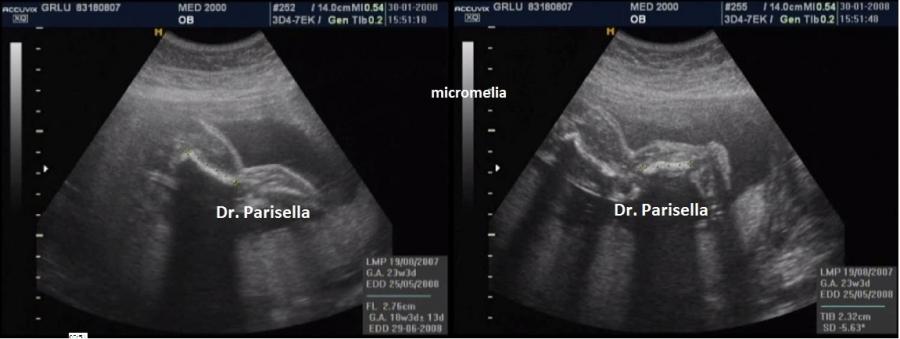

Micromelia

piede torto

Si manifesta con severa micromelia, ipoplasia toracica, piede torto, palatoschisi, micrognazia, pollici ed alluci addotti, scoliosi.